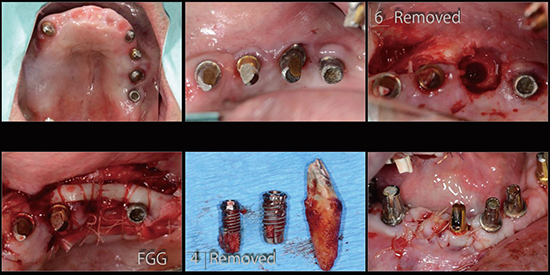

治療中04

治療中05

治療中06

治療中07